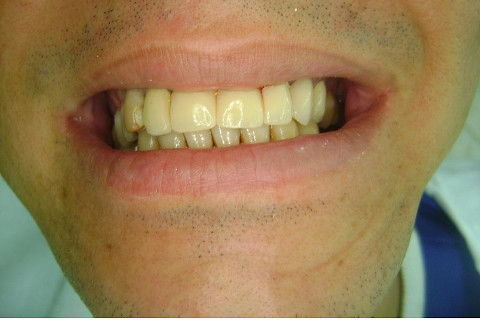

Paciente apareceu em meu consultório em dezembro/2013 para resolver problema de insatisfação com ponte fixa provisória anterior, realizada há 9 anos atrás (2004)...pretendia realizar somente a reabilitação em maxila/anterior, não contava com outros problemas com maior gravidade na sua boca, o máximo que citou foi a indicação para a exodontia do 16...